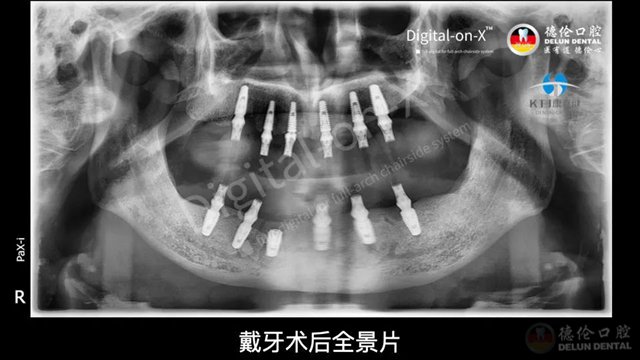

08 戴牙

DELUN DENTAL CLINIC